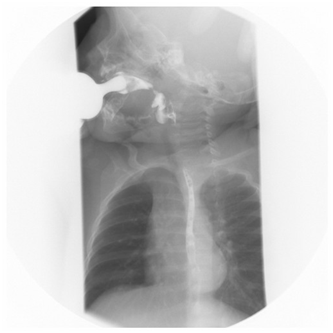

At six months of age, the swallowing study showed tongue motility disorders, slow oral transit, delayed onset of swallowing, barium laryngeal penetration, and 5 events of GER to the upper third of the esophagus (Figure 2). BAEP at 11 months of age showed I-III and I-V intervals latencies within the upper normality limits on the right ear, increased absolute latency of wave V and increased latency of intervals I-III and I-V of the left ear.9

Figure 2 Swallowing study at six months of age shows laryngeal penetration of the barium solution.